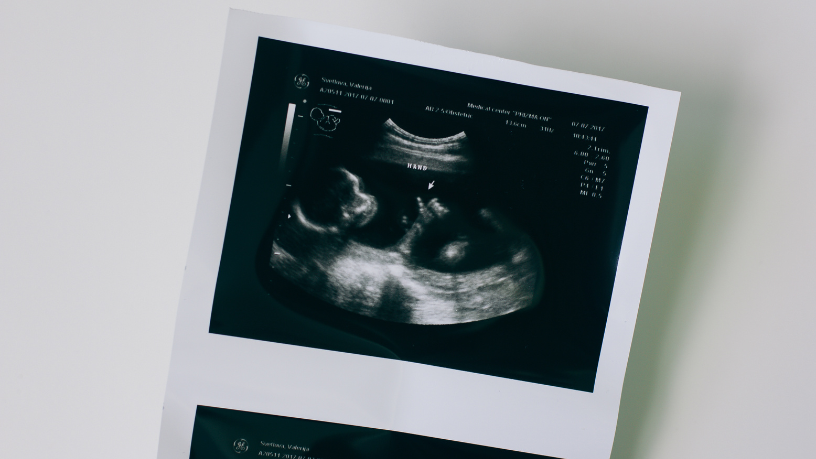

Diversos exames podem ser empregados na detecção de malformações fetais, sendo a ultrassonografia o principal método inicial. Ela é segura, não invasiva e indicada rotineiramente durante a gestação, permitindo avaliar o crescimento do feto e observar estruturas como cérebro, coração, rins e coluna. Tendo isso em vista, a ultrassonografia morfológica, realizada em momentos específicos da gravidez, é um dos principais recursos para investigar alterações estruturais, de acordo com Thaline Neves.

Outro exame de grande importância é a ressonância magnética fetal. Diferente do ultrassom, ela oferece imagens detalhadas em três dimensões, o que possibilita avaliar com mais clareza áreas complexas, como o sistema nervoso central. Esse exame costuma ser indicado quando há dúvidas nos resultados do ultrassom ou quando há necessidade de maior detalhamento. Conforme informa a Dra. Thaline Neves, a ressonância fetal amplia as chances de diagnóstico preciso em casos de suspeitas mais complexas.